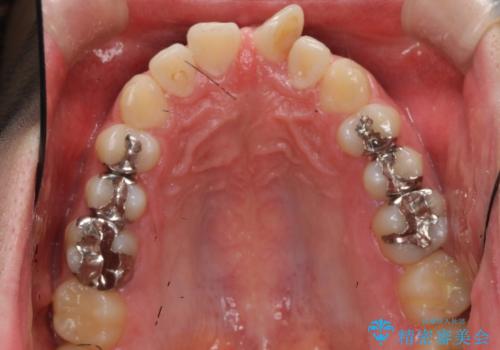

奥歯のかみあわせも問題なく、また、下の前歯のがたつきが元からない場合は上の部分矯正が十分可能です。

上下親知らずの抜歯や虫歯処置も矯正前後で行っています。